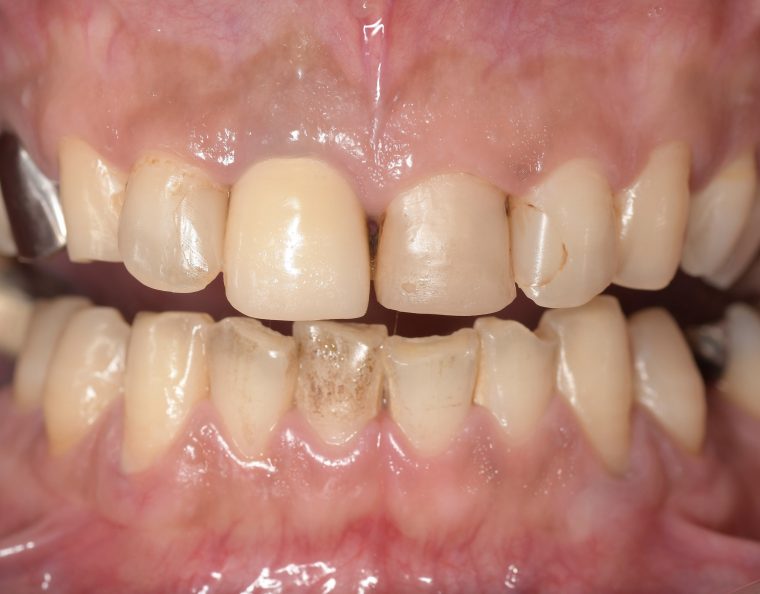

クリーニングの症例

現在の治療費と異なる場合がございます。最新の治療費は料金表をご確認ください。CASE 1

Before

After

基本情報

| 主訴 | 見た目をきれいにしたい |

|---|---|

| 治療期間 | 6ヶ月 |

| 治療費 | ジルコニアボンド(セラミックの被せもの)¥165,000×7(税込み) オフィスホワイトニング4回 ¥4,400×4(税込み) ホームホワイトニング¥11,000 |

| リスク・副作用 | かみ合わせがとても強い方の場合、稀に割れてしまうことがあります。 |

| 先生からの提案 | 上の前歯6本と右下の2番目の歯はセラミックの被せもので治療。 残りの下の前歯5本はプラスチックの材料で虫歯を治療し、 ホワイトニングをおこないました。白くなったご自身の歯の色に合わせてセラミックの 被せものを作成しています。 模型上で完成後をシュミレーションし、上の歯茎の位置をきれいに見えるように 揃えています。(外科処置はしていません) |